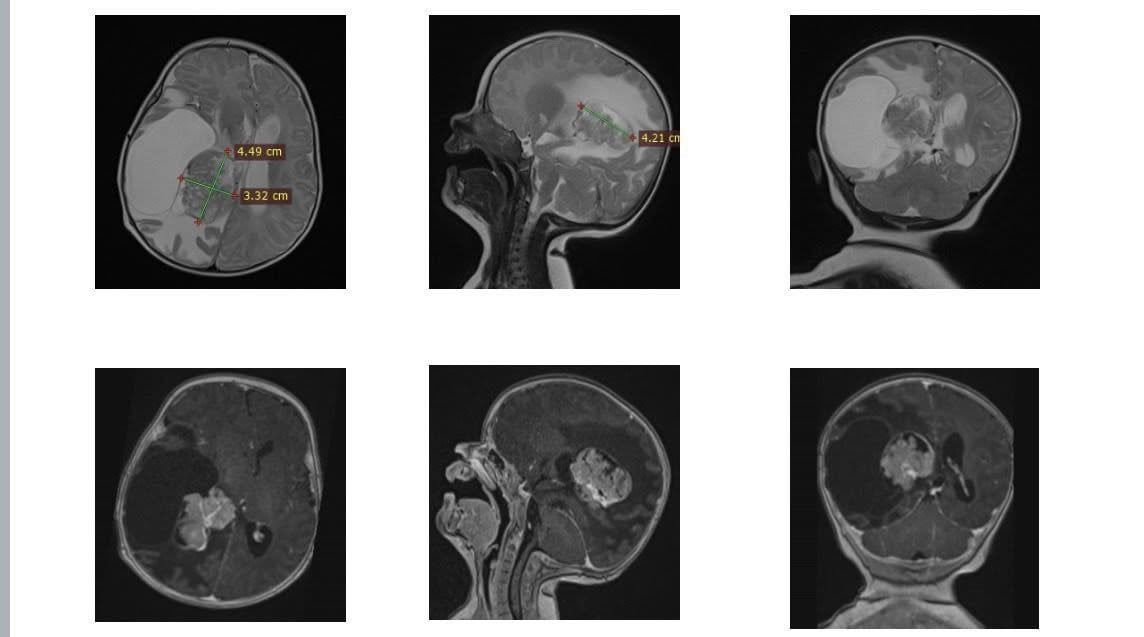

У Львові медики видалили пухлину у правому боковому шлуночку мозку двомісячної дитини.

У двомісячної Олівії з Рівного виявили пухлину у правому боковому шлуночку мозку. Дитина потребувала складного нейрохірургічного втручання.

«Утворення розташовувалося в зоні судинного сплетення з високим кровопостачанням, а отже, з високим ризиком значної крововтрати. До того ж пухлина була близько до ділянки, відповідальної за рухи. Тому операція вимагала максимальної точності та ретельної підготовки», — розповів керівник Клініки дитячої нейрохірургії Михайло Ловга.

Втручання тривало довше, ніж зазвичай: лікарям доводилося поетапно зупинятися, контролюючи крововтрату, та надзвичайно обережно видаляти утвір, щоб не пошкодити рухові зони мозку. Такі операції можливі лише за наявності інтраопераційного моніторингу та злагодженої роботи висококваліфікованої команди — нейрохірургів, нейрофізіологів, анестезіологів і операційних медсестер.